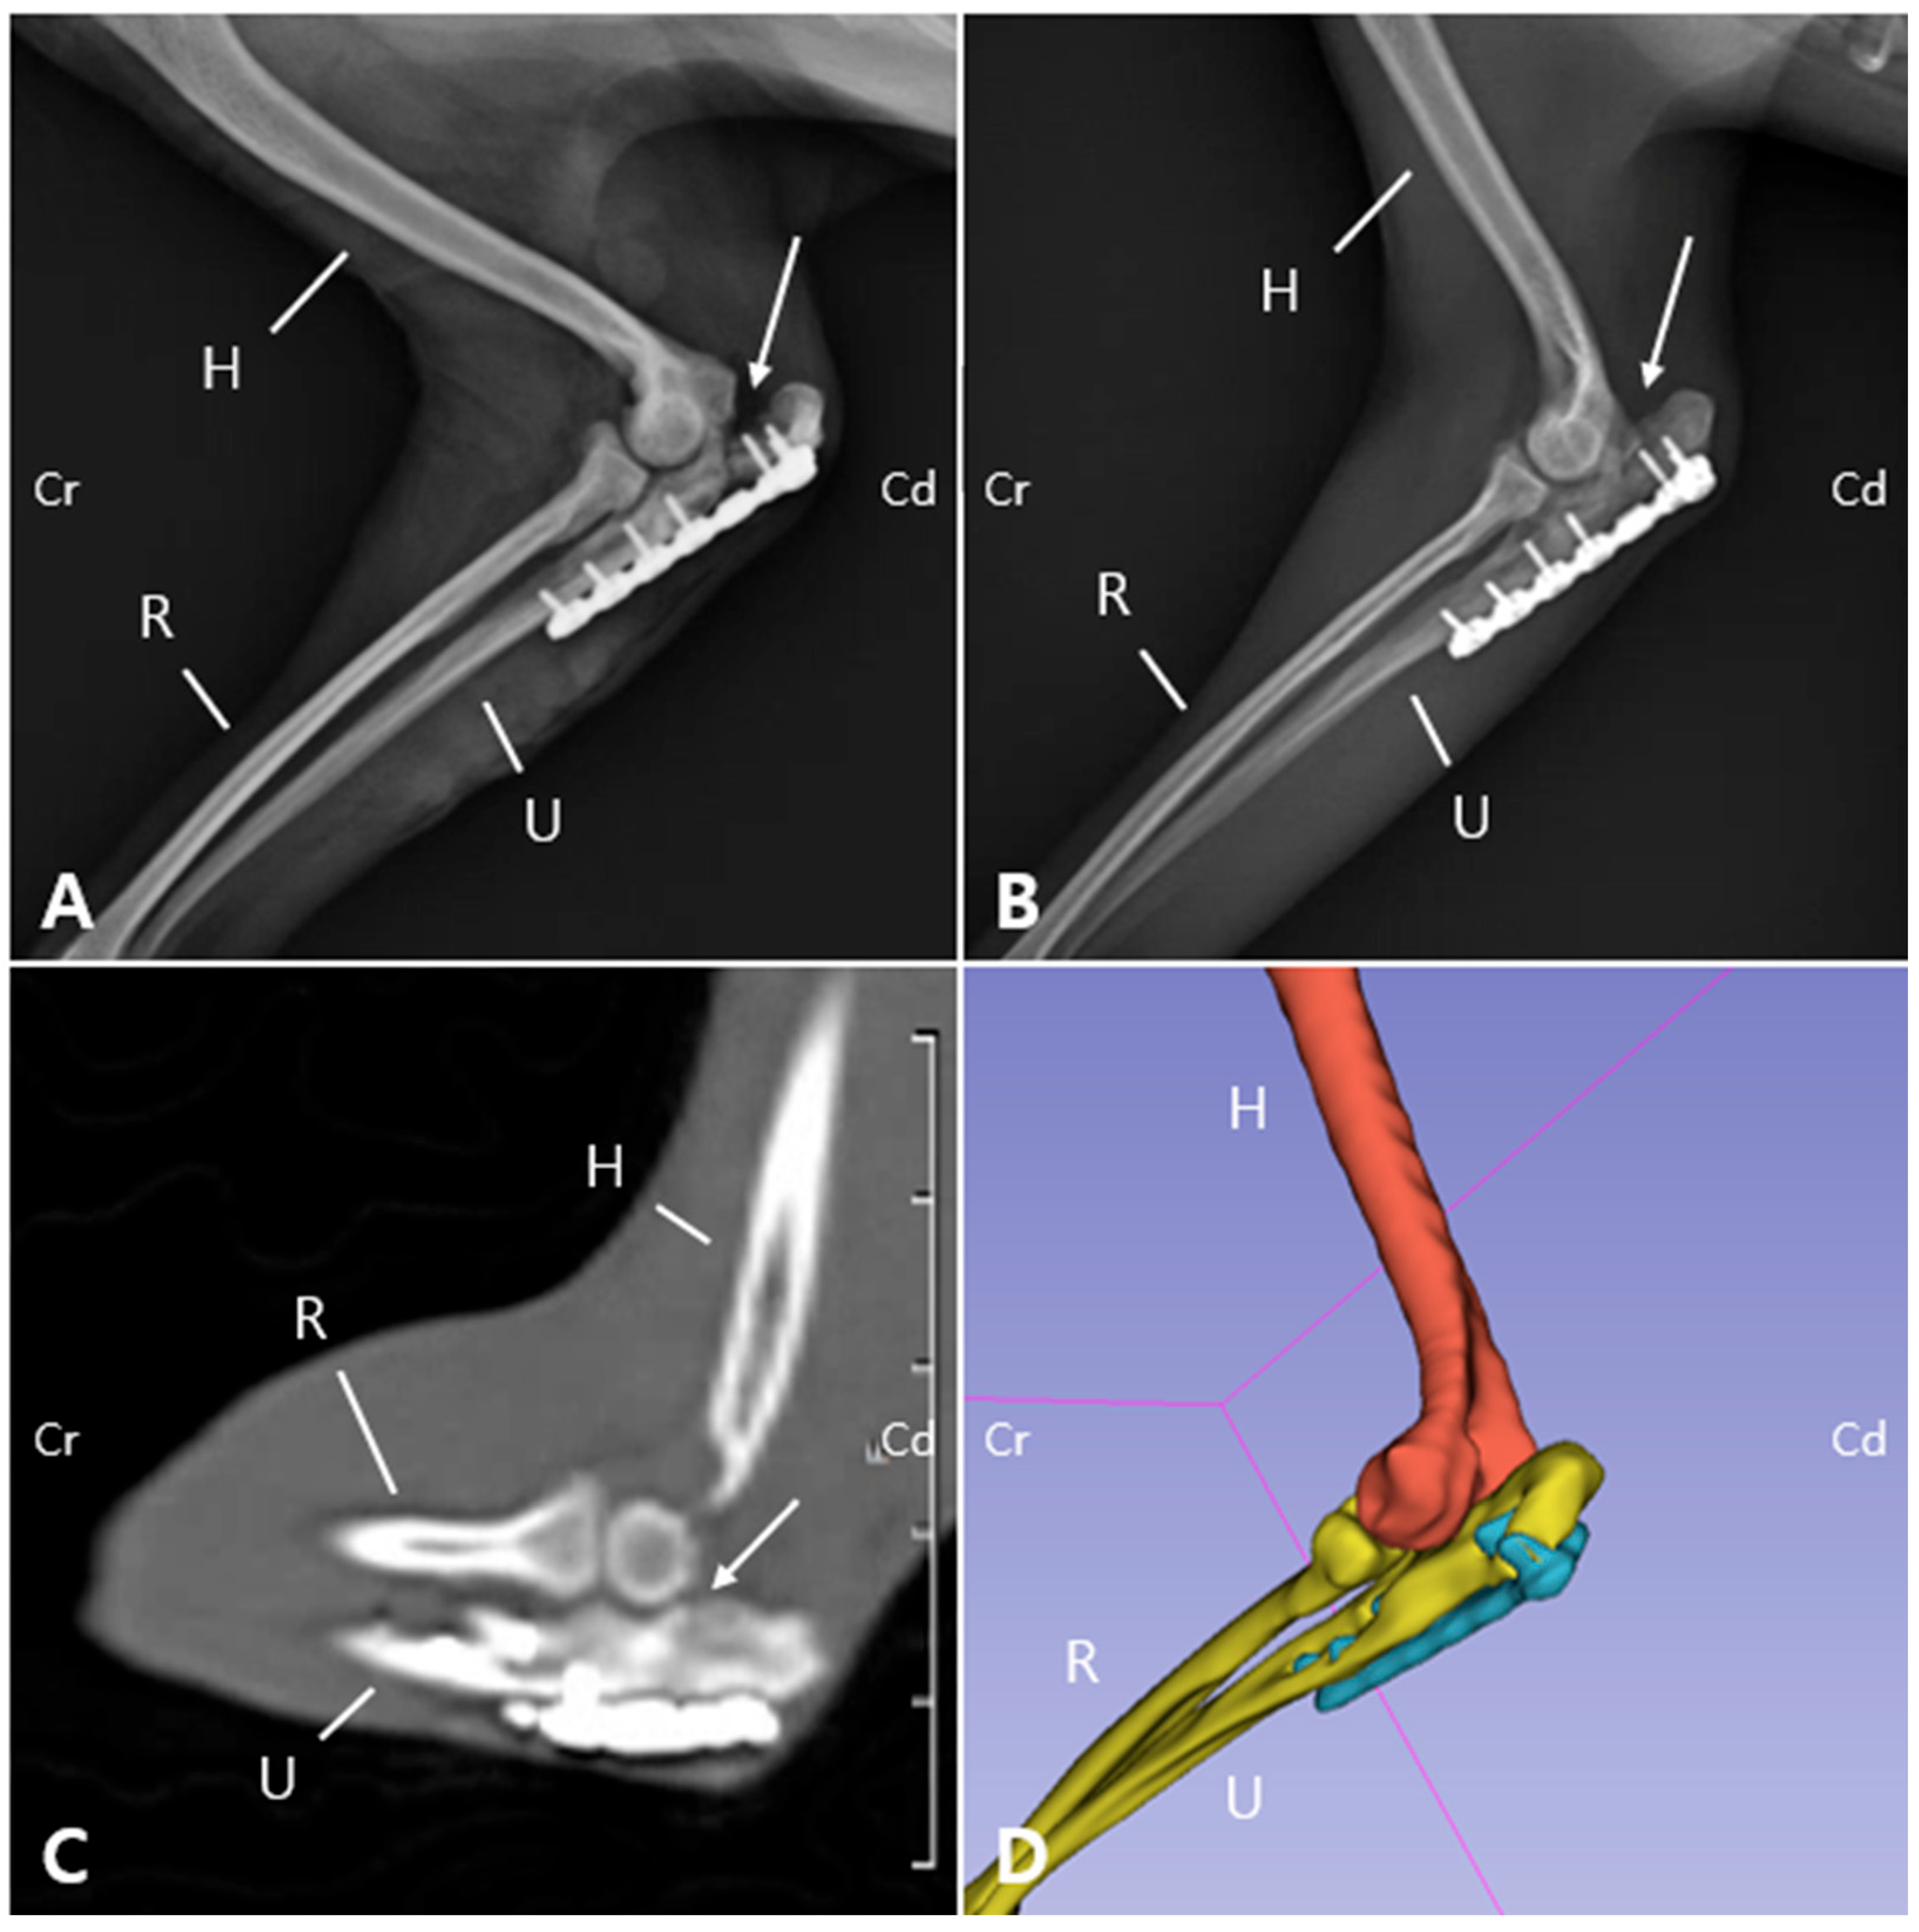

Radiographic and computed tomography (CT) imaging were obtained, revealing a fracture involving the olecranon of the left ulna, with ill-defined fracture margins and ulna luxation, while radiocapitellar alignment remained preserved. Additionally, sclerosis, osteolysis, deformation, and craniolateral displacement of the olecranon were observed. Sclerosis was also observed at the proximal diaphysis of the left ulna, with a well-defined, linear 3.0 mm bone fragment located caudally (Figure 1A,B). Soft tissue width was assessed on lateral radiographs by measuring soft tissue thickness at the midshaft of the humerus (brachium) and at the proximal one-third of the radius (antebrachium). In the right forelimb, the soft tissue width measured 48.69 mm at the brachium and 28.53 mm at the antebrachium, whereas in the left forelimb, the corresponding measurements were 32.25 mm and 21.04 mm, respectively. The values of the affected limb corresponded to 66.2% (brachium) and 73.7% (antebrachium) of those of the contralateral side. These results were consistent with the circumferential measurements and indicated muscle atrophy in the affected limb compared with the contralateral side. These findings indicated moderate muscle atrophy in the left forelimb compared to the contralateral side. Due to the chronic nature of injury, the fracture and luxation led to fibrosis of the surrounding joint tissues and chronic arthritis (Figure 1C,D), making it challenging to clearly identify the fracture anatomy and localization, which was important for surgical planning. Therefore, 3D modeling and printing were utilized to enable more precise preoperative planning.

2.3. Presurgical Plannings

To develop a surgical plan for olecranon fracture repair and joint reconstruction, 3D models were reconstructed from CT Digital Imaging and Communications in Medicine (DICOM) files using 3D Slicer 5.2.2 (Brigham and Women’s Hospital, Boston, MA, USA) (Figure 1E). The fractured olecranon and luxated elbow joint were then modeled using 3ds Max (Autodesk, San Francisco, CA, USA). Both the fractured and simulated repaired bone models were 3D printed using UV Tough resin and a 3D printer (Anycubic Photon M3 Max, Shenzhen Anycubic Technology Co., Ltd., Shenzhen, China) [20,21].

Figure 1. Preoperative radiographic, CT, and 3D reconstruction regarding the left elbow joint. On the anteroposterior radiograph (A), an olecranon fracture (arrow) and apparent dislocation of medial coronoid process (arrowhead) are evident. On the medio-lateral radiograph (B), the olecranon is displaced proximally (arrow), likely due to traction exerted by the triceps muscle. These images demonstrate a left olecranon fracture with associated ulnohumeral luxation. In the coronal and sagittal CT planes (C and D, respectively), periarticular fibrosis together with soft tissue proliferation at the fracture site impeded precise delineation of the fracture anatomy and localization. The 3D model (E) reconstructed from the CT data provides a clear structural depiction of the olecranon fracture and ulnar luxation. (M: Medial, L: Lateral, Cr: Cranial, Cd: Caudal, UO: Ulna olecranon, H: Humerus, U: Ulna, R: Radius).